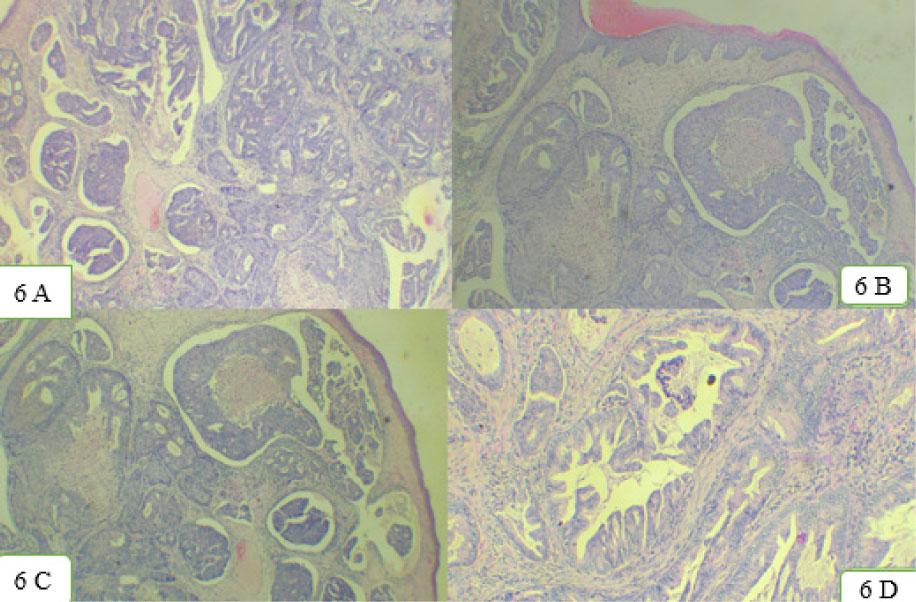

Incisional biopsy was performed, and on histopathological examination, pleomorphic tumor cells exhibiting hyper chromatic vesicular nuclei and eosinophilic cytoplasm were arranged in glandular, cribriform, and papillary pattern. Glands with intraluminal necrosis were noted along with lymphovascular and perineural invasion (Figure 6A–6D). The final diagnosis of well-differentiated intestinal sinonasal adenocarcinoma was rendered.

Histopathological images. 6A–6D: Pleomorphic tumor cells exhibited hyper chromatic vesicular nuclei and eosinophilic cytoplasm were arranged in glandular, cribriform, and papillary pattern. Glands with intraluminal necrosis were noted along with lymphovascular and perineural invasion.